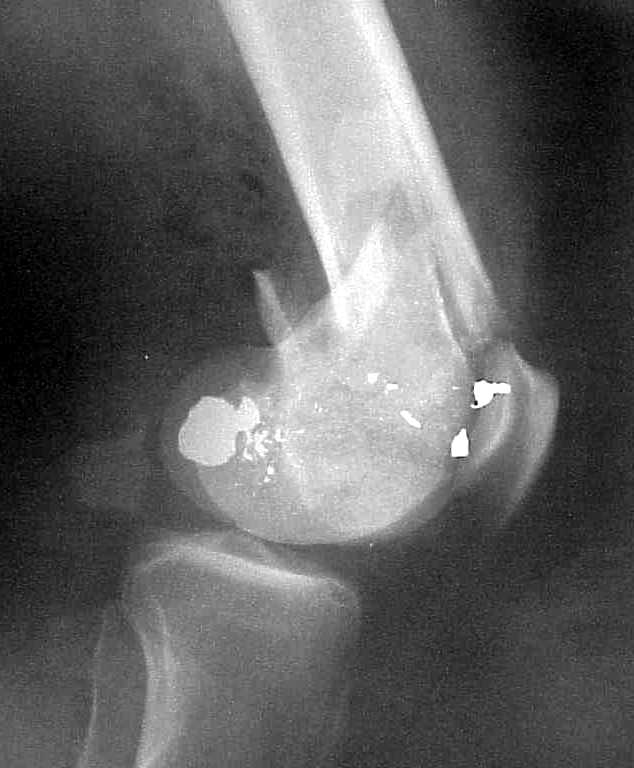

A CT and knee xrays would help identify lateral condyle comminution and/or a "hoffa fragment" of the posterior condyle. I am concerned that the lateral cortex is not sufficient to give purchase for a retrograde IMN. blocking screws could improve this as a possibility. A long blade or LISS if avaible would be my secondary choices. Good luck. Any chance you can get these cases transferred earlier when it

Lateral condyle looks too small for the blade, and the plate too short.